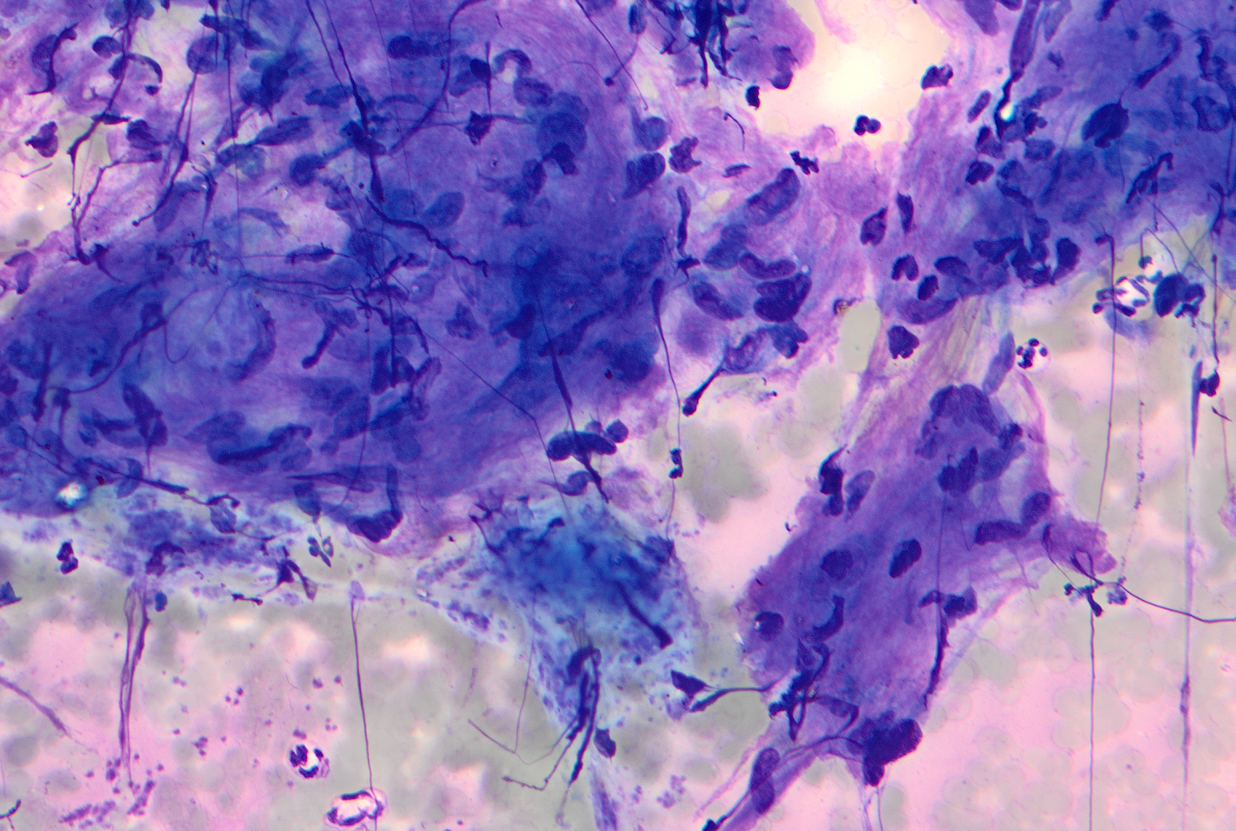

Figure 1: EBUS FNA of hilar mass, aspirate smear, Diff-Quik stained

Figure 2: EBUS FNA of hilar mass, aspirate smear, Diff-Quik stained

The FNA aspirate smears (Figure 1 to 4) show clusters of spindle shaped cells arranged in short fascicles with pale eosinophilic cytoplasm, and slender wavy or buckled nuclei. No significant nuclear atypia, mitotic activity or necrosis was identified. Variable amount of collagenous material separates these spindle cells. The cell block (Figure 5) shows cohesive tissue fragments, with fibrillary stroma and focal palisading of the spindle, wavy, or fish-hook–like nuclei with pointed ends. The spindle cells show fine chromatin, smooth and regular nuclear membranes, and inconspicuous nucleoli and bipolar spindle cytoplasm. Immunocytochemical stain performed on the cell block reveals that spindle cells are positive for S-100 (Figure 6). The cells also showed nuclear positivity for SOX-10, while they were negative for cytokeratin AE1/3 and CAM5.2, CD68, CD34, CD117, DOG1, ERG, MelanA, and HMB45 (Not shown).